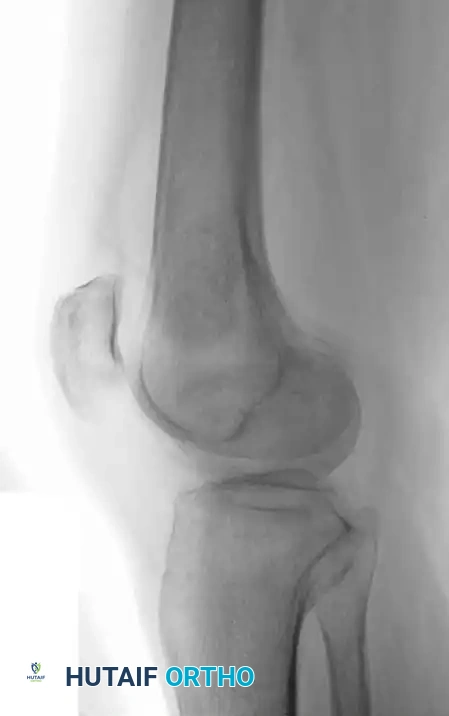

Fig. 20-22: (A and B) Pathological fracture of the right proximal tibia occurring through a large, expansile “brown tumor” of hyperparathyroidism in a 55-year-old woman.